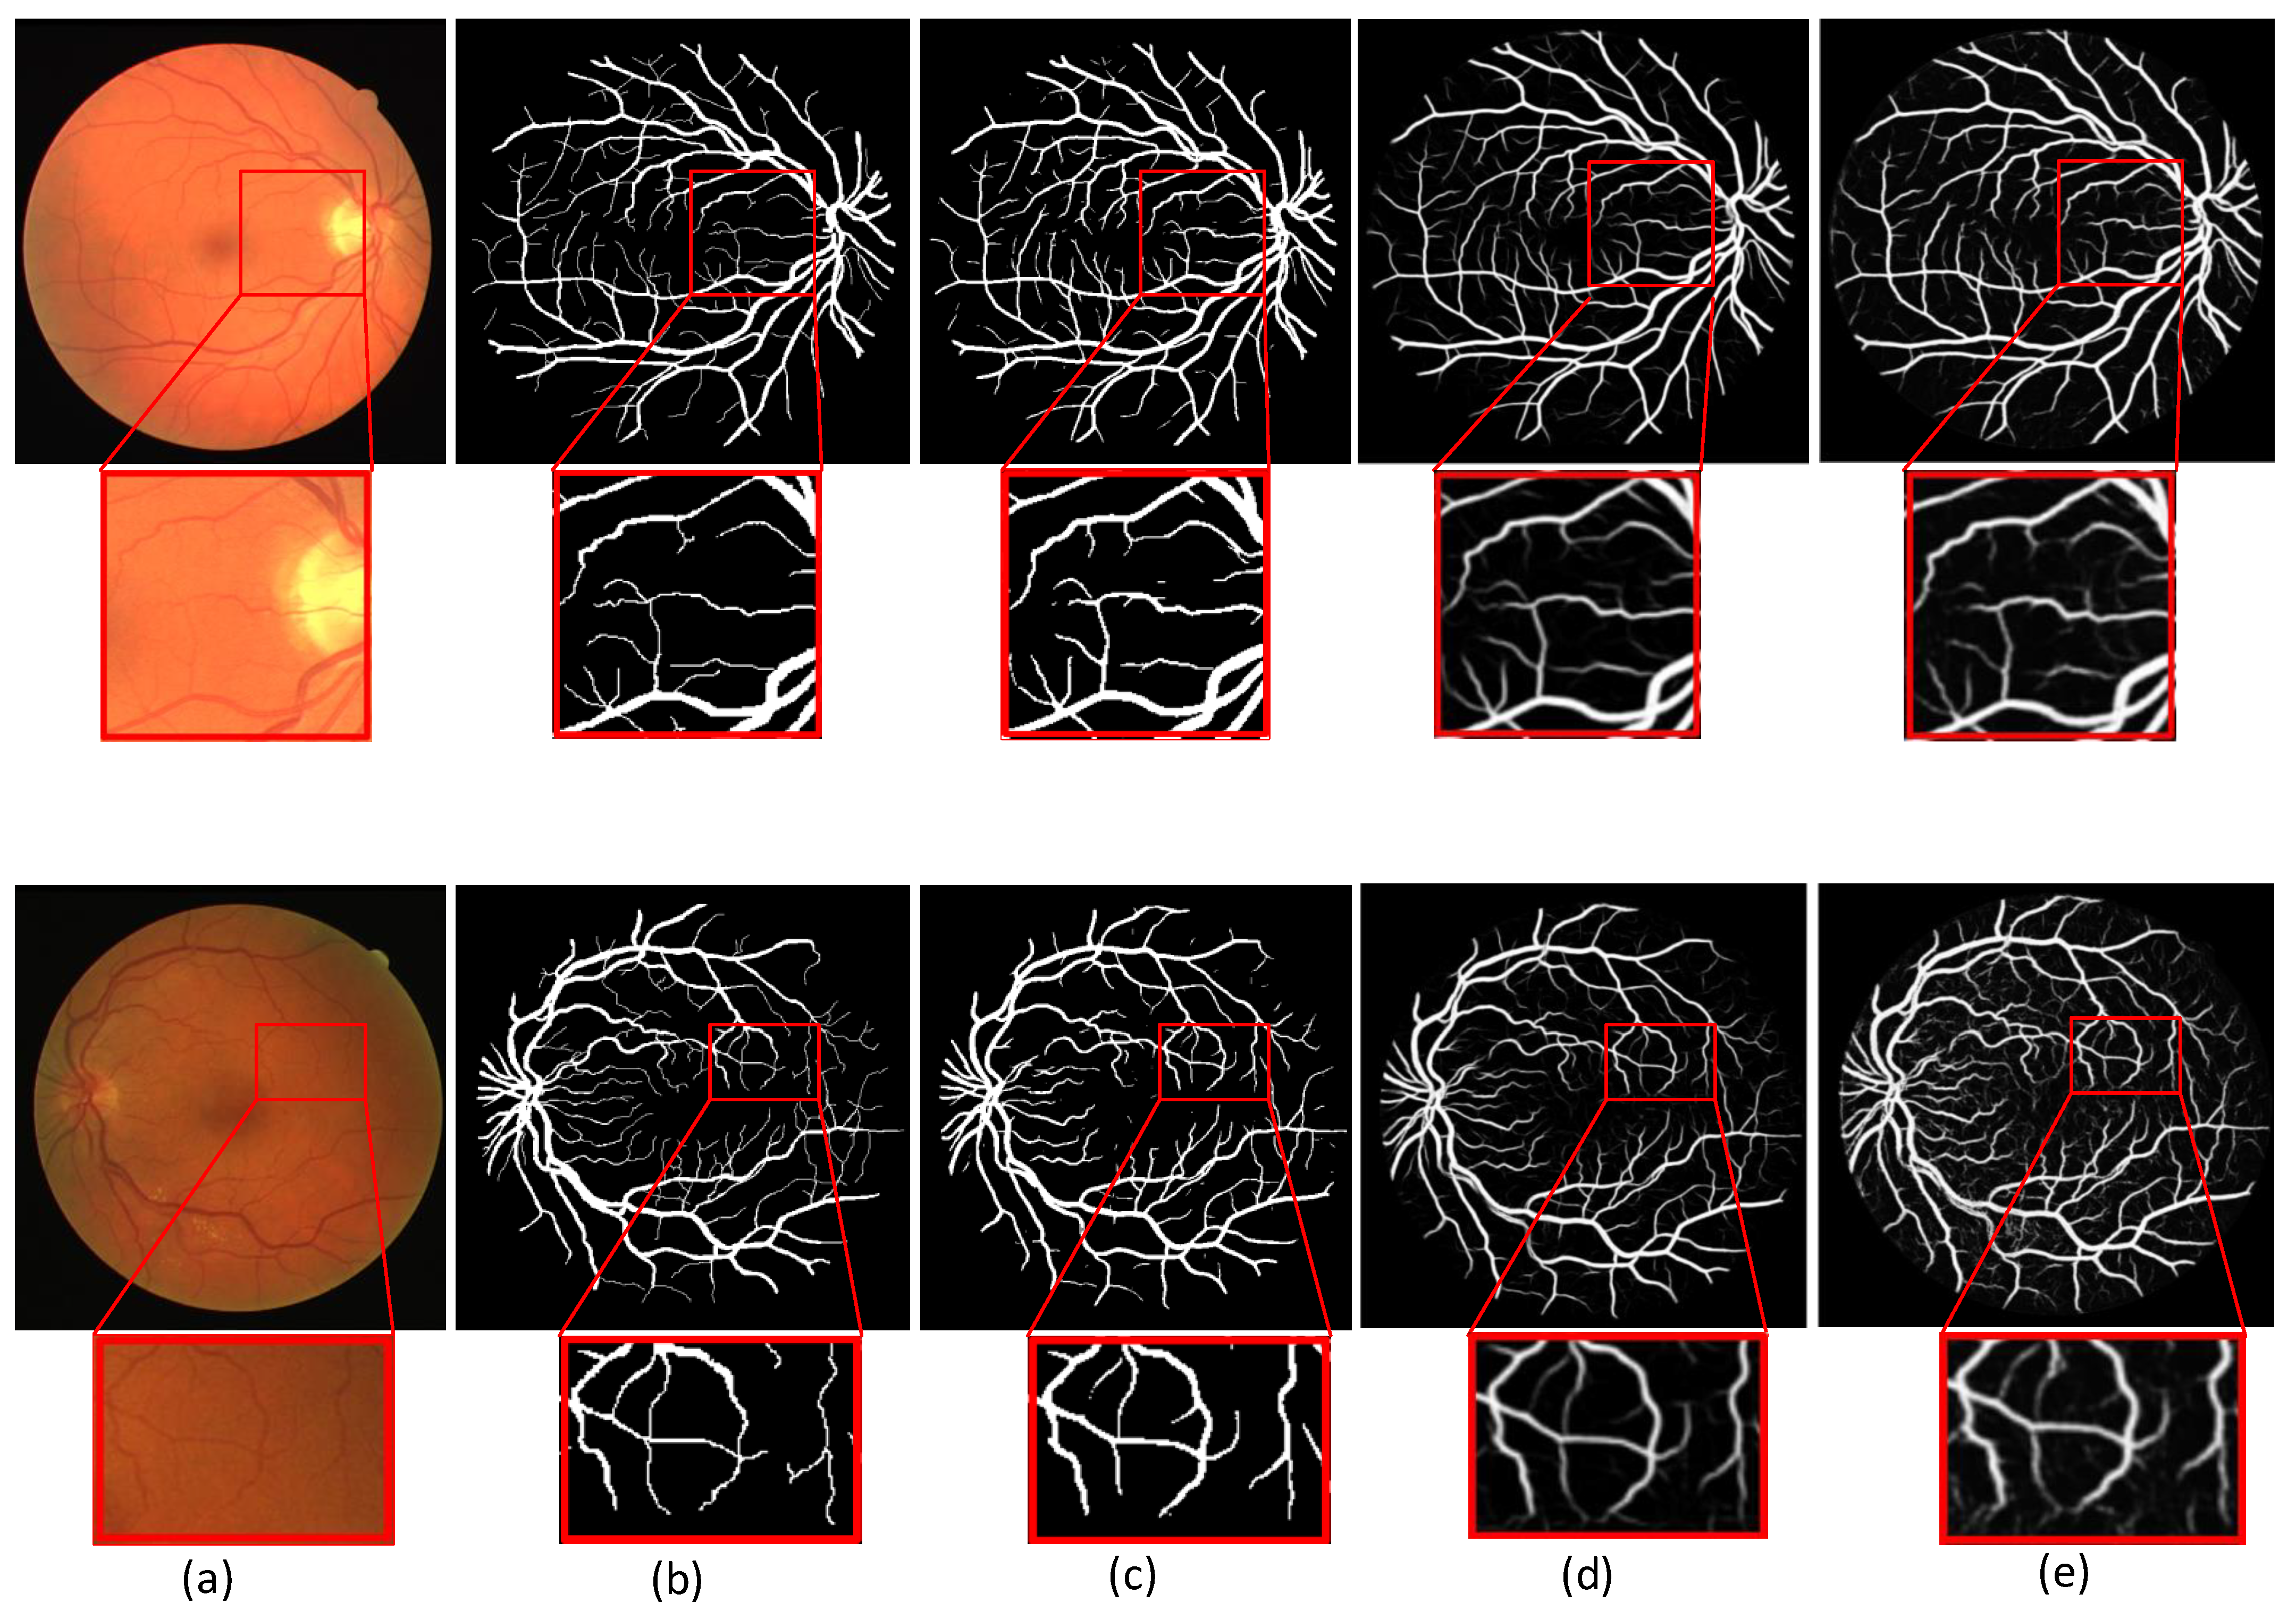

In the following experiments, MSMB-Net is compared with some existing methods (e.g., UNet, Ce-net). In this paper, the effectiveness of MSMB-Net is illustrated by comparing the visualization of MSMB-Net with the visualization of existing methods.

Figure 9 shows the segmentation visualization of two retinal images on the DRIVE dataset. The first line is an image of the retina of a diabetic patient. The second line is the retina image of a normal person. The red box in the figure indicates the local magnification part, and the difference with other models can be found with the magnified image. We observe that Unet and Ce-net have unclear and inaccurate segmentation of fine vessels. The visualization results show that MSMB-Net is effective for the segmentation of small blood vessels. The small blood vessels segmented by the UNet method are unclear and blurred. When the Ce-net method is used to segment retinal blood vessels, the segmentation of small blood vessels is slightly better than UNet. However, it is easy to mistakenly segment the diseased area into retinal blood vessels, resulting in a poor segmentation effect. In the method used in this paper, the SMCF module is used to expand the range of the receptive field and reduce the loss of characteristic information. Therefore, the characteristics of small blood vessels and lesion areas are better restored, which makes the segmentation result more accurate.

Figure 9.

Comparison of different segmentation results in the DRIVE dataset. (a) Image (b) Ground truth (c) MSMB-Net (d) UNet (e) Ce-net.